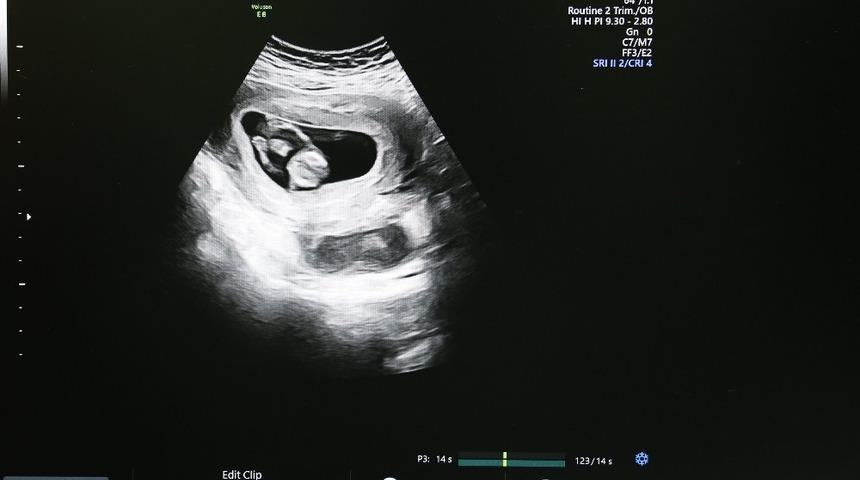

Sivas Cumhuriyet Üniversitesi Araştırma ve Uygulama Hastanesi, Kadın Hastalıkları ve Doğum Kliniği’nde yaklaşık 1 yıl önce hizmet vermeye başlayan “Ultrasonografi Cihazı” sayesinde anne karnındaki bebeğin bütün yapısal problemleri tespit edilebiliyor.

Cihaz sayesinde anne karnındaki bebeklerde zor ve güç olan problemleri kolaylıkla görüntüleyebildiklerini anlatan Doç. Dr. Çağlar Yıldız, “Bebeğin vücut yapısında bulunan tüm problemleri tespit edebiliyoruz. Örneğin; kalp, beyin gelişimiyle ilgili problemleri, kol ve bacak, yüz deformiteleriyle ilgili problemleri rahatlıkla ortaya koyabilmekteyiz” şeklinde konuştu.